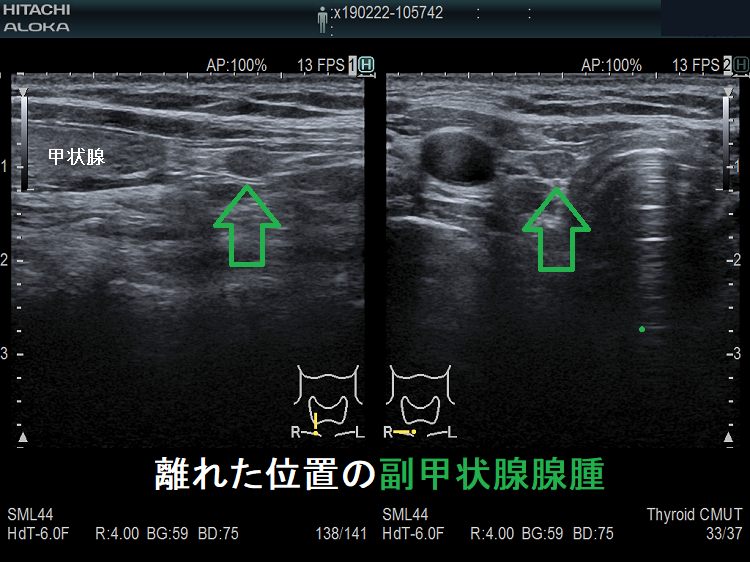

(➸)原因となる副甲状腺腺腫、副甲状腺癌、副甲状腺過形成をデジタルハイビジョン超音波診断装置で診断。エコーでは、甲状腺とのインピーダンスの違いにより、甲状腺-副甲状腺境界部に線状高エコーが生じます(右図の↓)。内部は中心血流を認め、リンパ節でないのが分かります。

微小副甲状腺腫;血清カルシウムは正常範囲内の上限だが、脱水などの影響で上限を超える場合もある。骨密度は正常で、腎結石(腎臓結石)もない。

超音波(エコー)検査で見つからない副甲状腺は、

- 縦隔内

- 食道背側

- 喉頭背側

に存在する場合です。